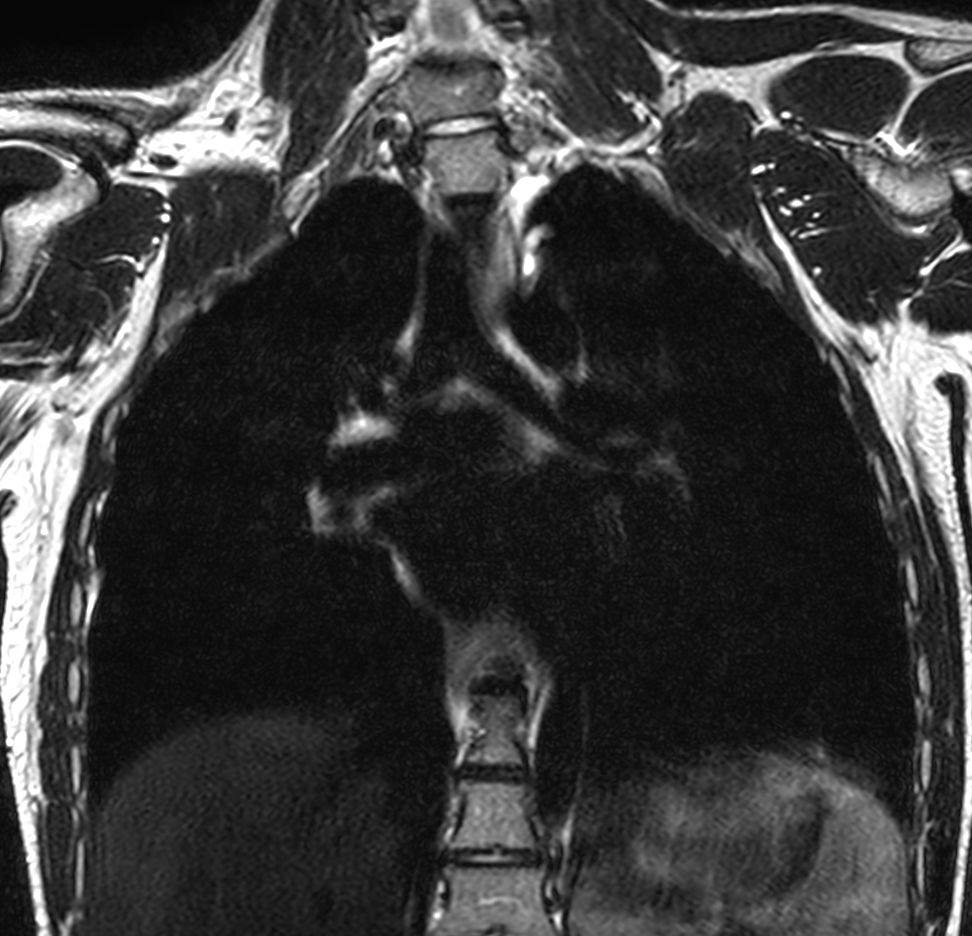

T2w TSE